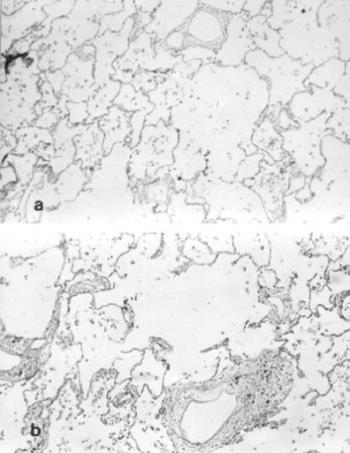

- Szövettani vizsgálatok múmia-szöveteken